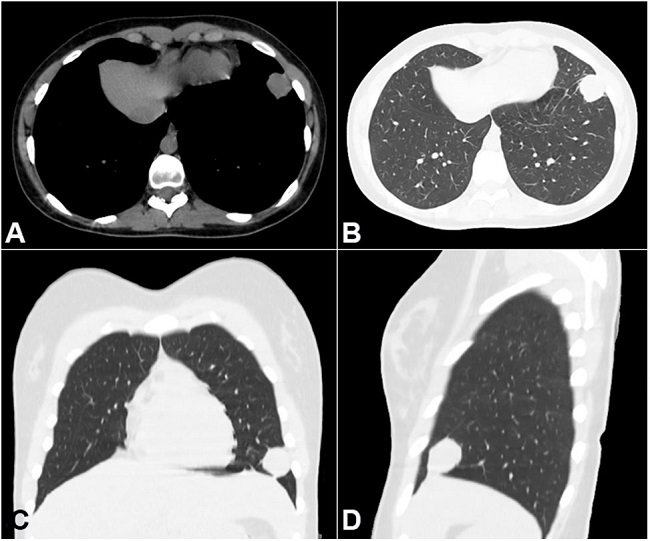

A 25-year-old woman sought medical attention complaining of chest pain, with characteristics of pleurisy, at the base of the left hemithorax, which had progressed over the last 6 months. Initially, the symptom was intermittent and of variable duration. She denied fever or weight loss. Her past medical history included asthma and a papillary thyroid carcinoma, which was resected 8 years ago, with no evidence of relapse to date. The physical exam was normal except for the presence of a central neck scar. A chest radiograph (Figure 1) showed a round opacity (coin lesion) at the base of the left pulmonary inferior lobe, which, on the thoracic computed tomography (Figure 2) was revealed to be a peripheral lesion in close contact with the pleura, measuring approximately 2.5 cm in its longest axis.

As in the patient reported herein, pulmonary histoplasmoma occurs as an isolated coin lesion on the chest x-ray.26 Unfortunately, the calcification deposits were not depicted by the imaging examinations. When present, the pattern of calcification is helpful to the diagnosis, as the calcium deposits in concentric rings, or those found in the center of the lesion, are highly consistent with the diagnosis.27 Also, calcified lesions are encountered more frequently in histoplasmoma than in tuberculoma.15 However, their presence is not an essential finding.28